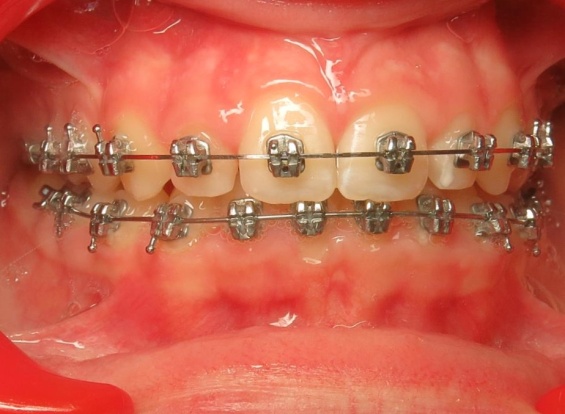

3 - Phase 2 : traitement orthodontique- alignement des dents et occlusion

Le traitement a d’abord consisté à corriger le décalage entre les bases osseuses des mâchoires par une phase orthopédique. Une fois cet équilibre rétabli, un appareil multiattaches a été mis en place pour aligner les dents sur des bases désormais bien positionnées. La dernière étape a permis de peaufiner les contacts entre les dents afin d’obtenir une occlusion fonctionnelle et stable.